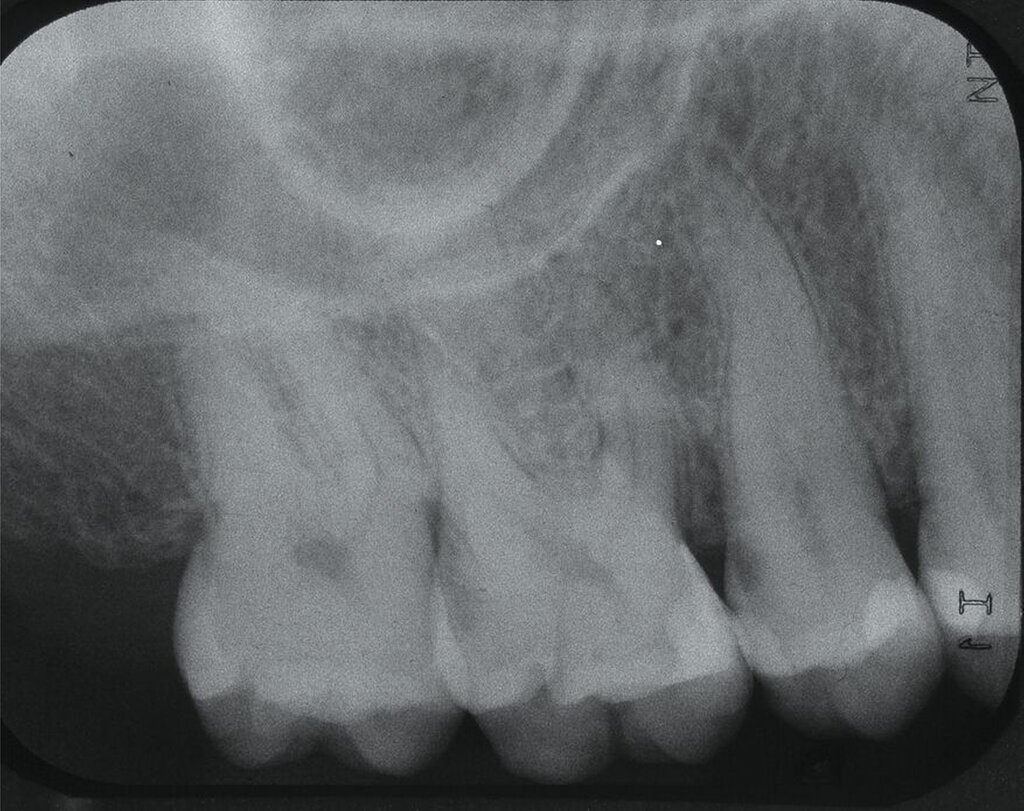

Systemische Faktoren, die den Erfolg regenerativer Maßnahmen beeinflussen können, sind beispielsweise ein unkontrollierter Diabetes oder eine eingeschränkte Immunabwehr. Verhaltensfaktoren wie Rauchen, unzureichende Mundhygiene und mangelnde Adhärenz müssen ebenfalls bei der Fallauswahl berücksichtigt werden. Zu den anatomischen beziehungsweise Defektfaktoren, die sich einigen Studien zufolge und nach Expertenkonsens negativ auf die Erfolgsaussichten einer regenerativen Furkationstherapie auswirken können, werden gezählt: ein erschwerter Zugang zum Operationsbereich, ein approximales Knochenniveau, das sich auf derselben Höhe oder sogar apikal des Furkationsdaches befindet, ein kurzer Wurzelstamm, ein enger Abstand zwischen den Wurzeln mit erschwerter Instrumentierung, eine deutlich erhöhte Zahnbeweglichkeit, ein dünner gingivaler Phänotyp, wenig keratinisiertes Gewebe, die Nähe eines Restaurationsrandes zum Furkationseingang und das Vorliegen einer gingivalen Rezession im Furkationsbereich.

2. Auswahl des Zahnes

Ein adäquater Zugang zum Operationsbereich und auch für die zukünftigen Mundhygienemaßnahmen ist äußerst wichtig. Molaren mit Grad-II-Furkationsdefekten (mandibulär und bukkal maxillär) sind Kandidaten, die für ein regeneratives Verfahren infrage kommen. Basierend auf der verfügbaren Evidenz sind interdentale Grad-II-Furkationsdefekte an Oberkiefermolaren deutlich weniger geeignet, höchstwahrscheinlich aufgrund des eingeschränkten Zugangs. Weitere lokale Charakteristika können Auswirkungen auf die Ergebnisse der regenerativen Furkationschirurgie haben. Zum Beispiel können ein dickerer Phänotyp und das Fehlen einer Weichgeweberezession die Heilung nach GTR-Verfahren positiv beeinflussen. Günstigere Ergebnisse sind an Stellen zu erwarten, an denen das verbleibende approximale Knochenniveau koronal zum Eingang beziehungsweise zum Dach des Furkationsdefekts liegt, verglichen mit solchen, bei denen das approximale Knochenniveau auf der Höhe oder apikal des Furkationseingangs liegt. Ein enger interradikulärer Abstand kann eine gründliche Defektinstrumentierung beeinträchtigen. Das Vorhandensein einer Wurzelkanalfüllung ist nicht per se eine Kontraindikation für die Furkationsregeneration – vorausgesetzt, es gibt keine Anzeichen für apikale pathologische Veränderungen.